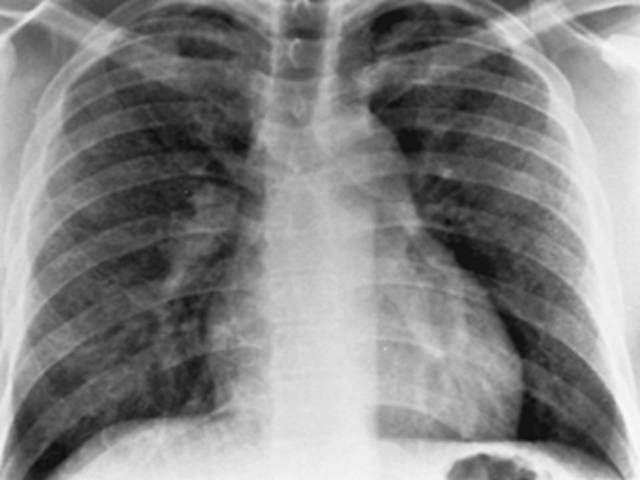

• Neumonía atípica

Neumonía atípica

Aparece en China la neumonía atípica (síndrome respiratorio agudo, SARS), enfermedad respiratoria producida por un coronavirus.